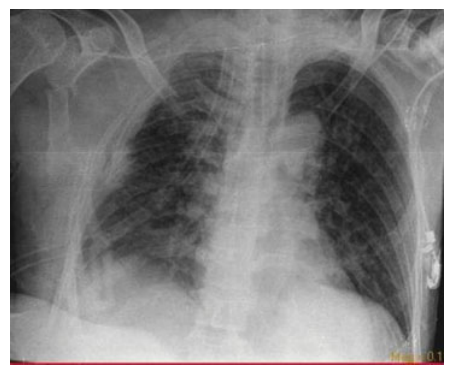

一名53岁的男性患者,因高处掉落的建筑材料砸中右肩和胸部区域而被送往急诊科。初步体检显示患者右肩部有表皮擦伤和广泛的皮下气肿,右前胸壁有一大约10×15 cm的连枷胸区域,并伴有呼吸困难。胸片显示右侧多根肋骨、锁骨和肩胛骨骨折,右侧液气胸以及广泛的皮下气肿(►图1和图2)。

图1. 患者置入胸腔引流管后的胸片。